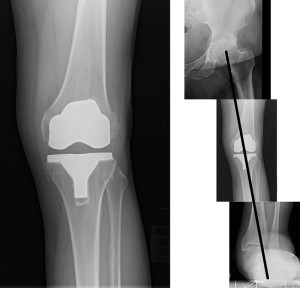

Mr. P has a history of progressive pain in both the knee and ankle over the past few years, resulting from lateral knee osteoarthritis (OA) and adult acquired flatfoot deformity. He is aged 61 years and significantly overweight (6 ft, 2 in, 282 pounds). He is not diabetic but has a diagnosis of atrial fibrillation and has been taking warfarin for years. He avoids exercise at all costs. He has tried numerous types of orthotic devices without relief of his symptoms. He is not interested in physical therapy. Weightbearing anterior-posterior radiographs of his knee, ankle, and foot are depicted in Figure 1.

The aforementioned GRF vector in the coronal plane that represents loading of the joints of the lower extremity is referred to as the weightbearing axis11 (Figure 2). The normal weightbearing axis passes through the center of the hip joint, the center of the knee joint (anterior tibial spine), and the center of the ankle joint. This normal alignment of the weightbearing axis is predicated on the calcaneus being positioned in a normal relationship to the talus and ankle. Posterior tibial tendon insufficiency, with the resulting acquired flatfoot deformity, is characterized by a lateral displacement of the calcaneus relative to its normal relationship to the talus and ankle. This lateral displacement of the heel causes the vector of the weightbearing axis to be shifted laterally relative to its normal position during stance phase of gait (Figure 3).

Figure 3. Weightbearing axis in Mr. P. Note that the valgus deformity at the foot and ankle level allows the weightbearing axis to pass lateral to the normal knee center through the lateral joint compartment.